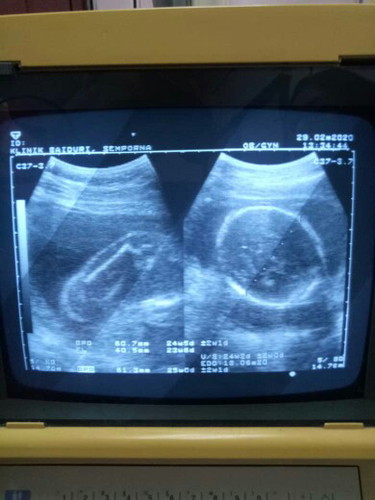

assalamualaikum mommies semua harap semua ny dlm keadaan sihat walafiat..ni nak tnya sya tgh prggy 23 weeks tp smlm scan doc ckp kandungan mcm 25weeks.. sy risau baby dlm perut besar...ada tips x tuk maintain ny berat baby dlm kandungan

Baca lagiSye bru buat details scan smalam. So far everything ok. Doc pun ckap baby sye besar 1w dari sepatutnya. Tpi doc ckap normal klau + - sminggu besar or kecik. Nnt lama kelamaan size tu akan balance dgn usia kandungan. Jgn risau ye sis. Dlm masa sama jaga pemakanan juga 🤗

Sma mcm sy baby besar dua mnggu..normal doktor bgthu..lepas tuh scan selepas sebulan dah maintain..sy kurangkan manis je..trsa nk minum sejuk pun letak air mineral dlm peti..selagi ta memudaratkn sis jgn bimbang think positive je..baby sihat alhamdulillah..